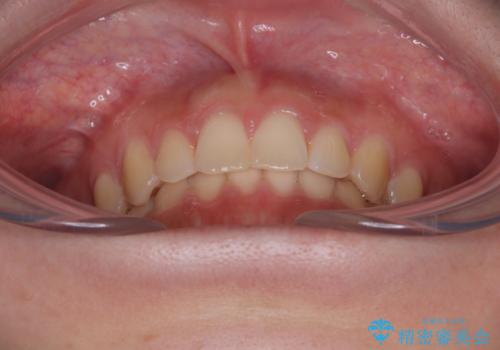

前歯のすきっ歯を治したい インビザラインによる矯正治療

- 上顎前歯の隙間を気にして来院された患者様です。

目立たない装置を希望とのことで、インビザラインを用いて矯正治療を行うこととしました。

最終的には隙間は全て閉じ、綺麗な仕上がりとなりました。